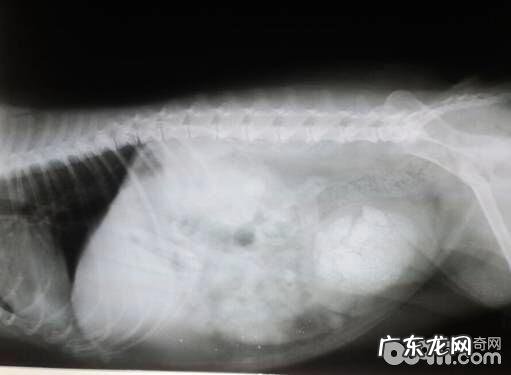

文章插图

X光片,一个病案中膀光内尿结石 。